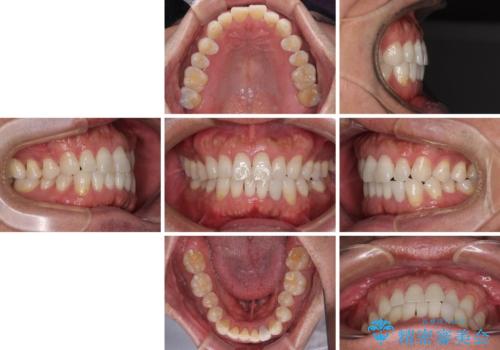

内側にある歯が干渉する 上顎前歯の部分矯正

- 上顎の前歯が内側にあり、下顎のセラミッククラウンと干渉することが気になるとのことで来院された患者様です。

上顎前歯にワイヤー装置を装着し、セラミッククラウンとは干渉しないようにしながら歯列を整えることとしました。

セラミッククラウンとの干渉はすぐに改善され、歯列も整いましたが、一方で、前歯で食事が噛みにくくなり、1年近い治療期間となりました。